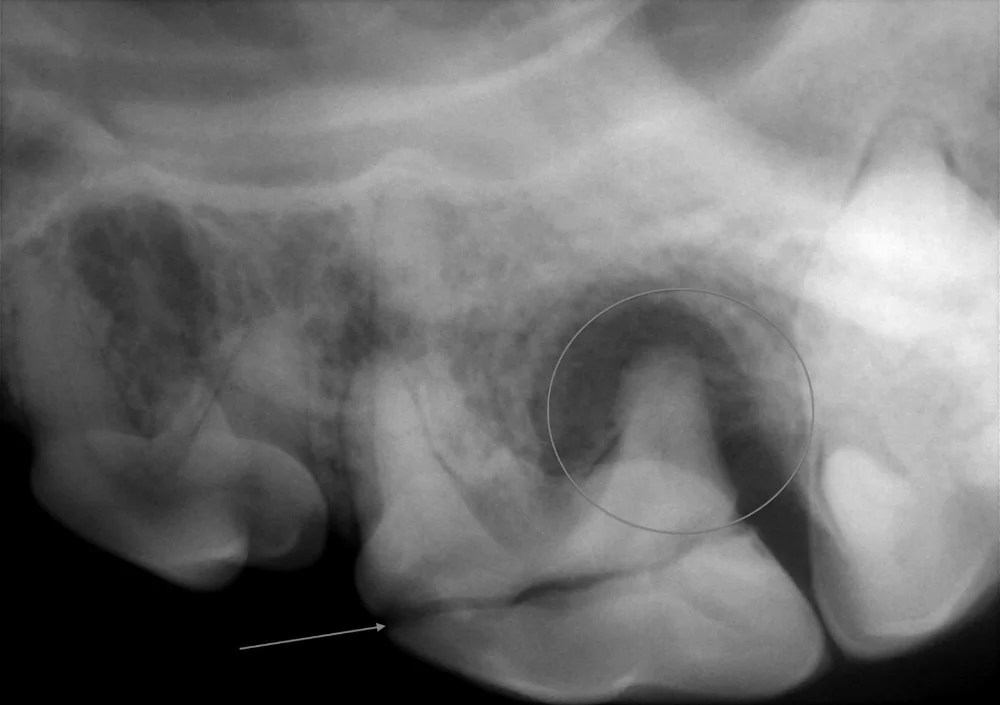

This tooth was fractured at the outside crown of the tooth (see arrow). Dental x-rays of the tooth showed significant infection (dark area circled) at the root of the tooth. Having this information helped plan the proper extraction technique of this badly damaged tooth.